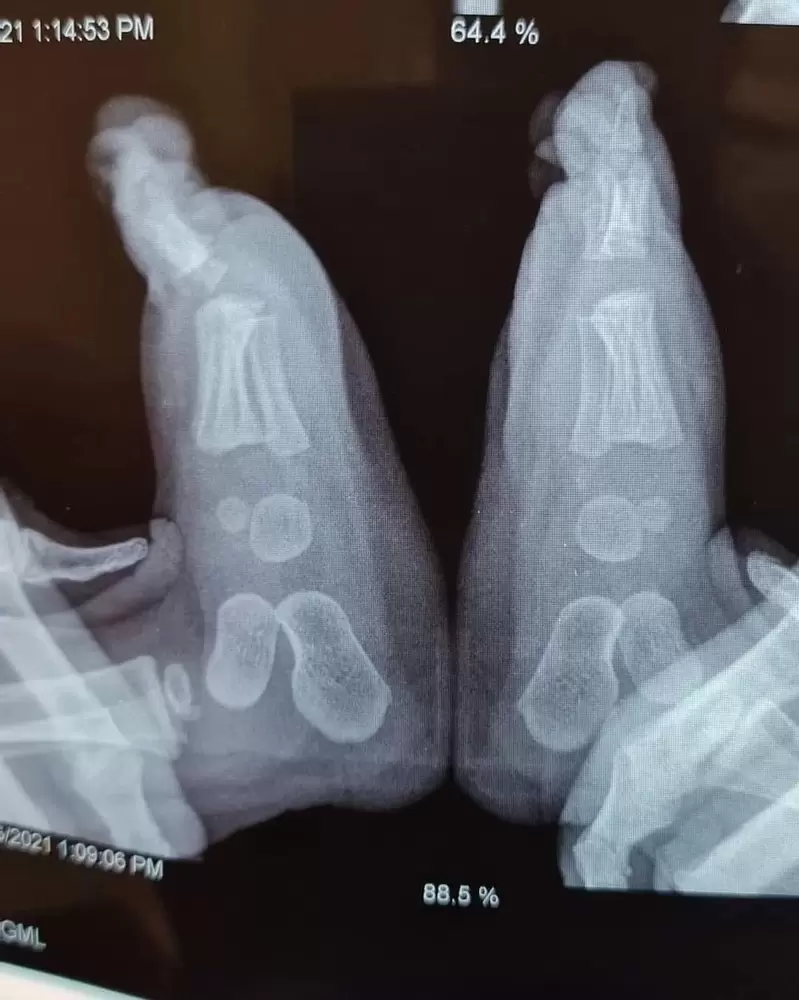

▼小嬰兒的手

圖片來自:buzzfeed

▼一個10個月大的嬰兒腳腳